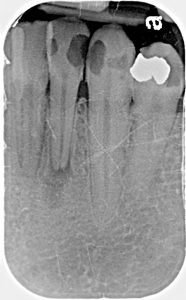

X Ray Of Abcess | Bellingham Dentist | Dental Implants | Northside Dental Care

Abscess X-ray

A tooth is composed mainly of hard tissue, (dentin, enamel, and cementum), but a small hollow portion in the center of the tooth contains nerves and blood vessels.  This inner part of the tooth is called the dental pulp, or just the pulp. Loss of blood supply to the pulp, which commonly happens due to trauma to these delicate tissues, allows an endodontic abscess to start forming. The blood contains white blood cells, one of our body’s primary defense mechanisms from bacteria. Therefore, loss of blood supply to the pulp allows growth of anaerobic bacteria inside the tooth, within the pulp chamber and associated root canal spaces.  The nerves and blood vessels enter the tooth through tiny openings at the root tips of the teeth, called the root apices. When an endodontic abscess forms, it is called a “periapical abscess.” Root “peri” means around and root “apex” means high point, therefore a periapical abscess is an abscess formed around the root tip of a tooth.

Endodontic abscesses can be quite painful when infection mounts rapidly; the confined space within the tooth and dense bone around the roots combined with accumulation of pus and other inflammatory byproducts may cause intense pressure on the nerves and periodontal tissue surrounding the tooth. This is referred to as an “acute abscess.” Conversely, when a tooth infection develops slowly, very little or no discomfort may be felt. This type of “painless infection” is called a “chronic abscess.” Chronic abscesses can be present for months or years without the patient knowing, as no pain is ever created. Sometimes draining of the infection through the gum tissue into the oral cavity may cause a sour taste in the mouth. This is sometimes the only sign that a dental abscess is present. This type of abscess is therefore usually discovered by radiographic examination at a routine dental visit.